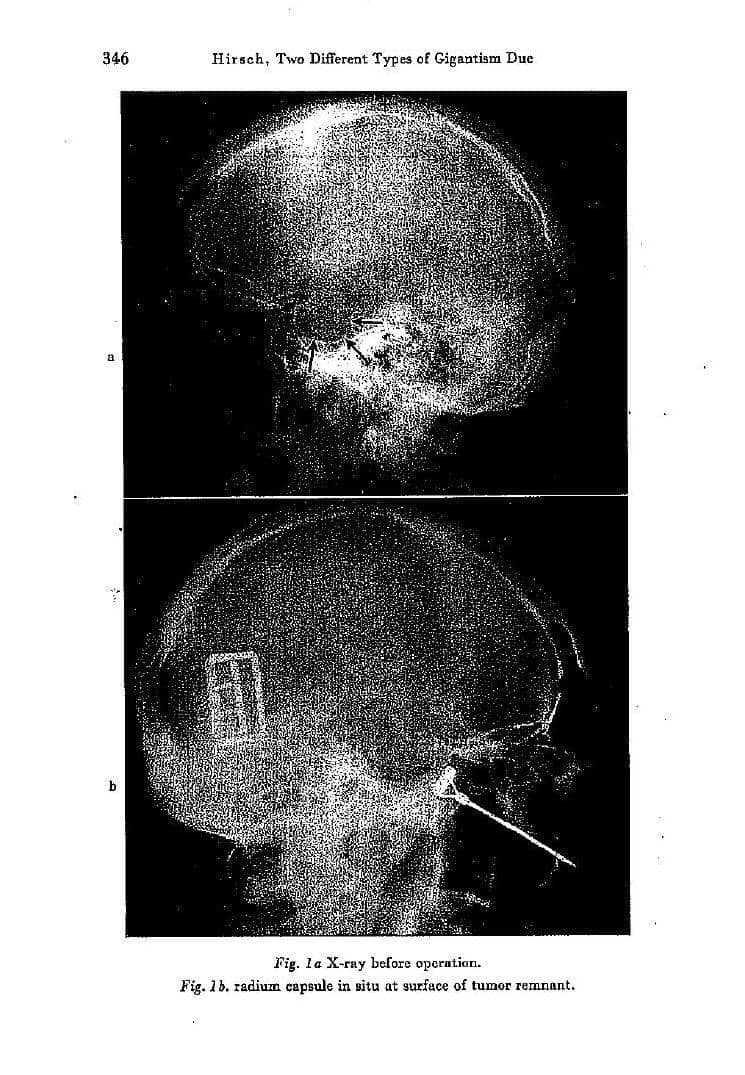

Pada Desember 1930, ketika Rainer berusia 31 tahun, seorang ahli bedah otak menganestesi Rainer secara lokal dan menaruh suatu alat ke dalam hidungnya, untuk memperoleh akses ke kelenjar pituitary-nya, sebuah struktur kecil yang berlokasi di daerah yang susah dijangkau dalam otak.

Ahli bedah tersebut menemukan eosinophilic adenoma, sebuah tumor jinak yang menekan bagian pituitary tersebut. Prosedur ini secara drastis memperlambat pertumbuhan Rainer, tapi telah banyak kerusakan tubuh yang sudah telanjur terjadi.